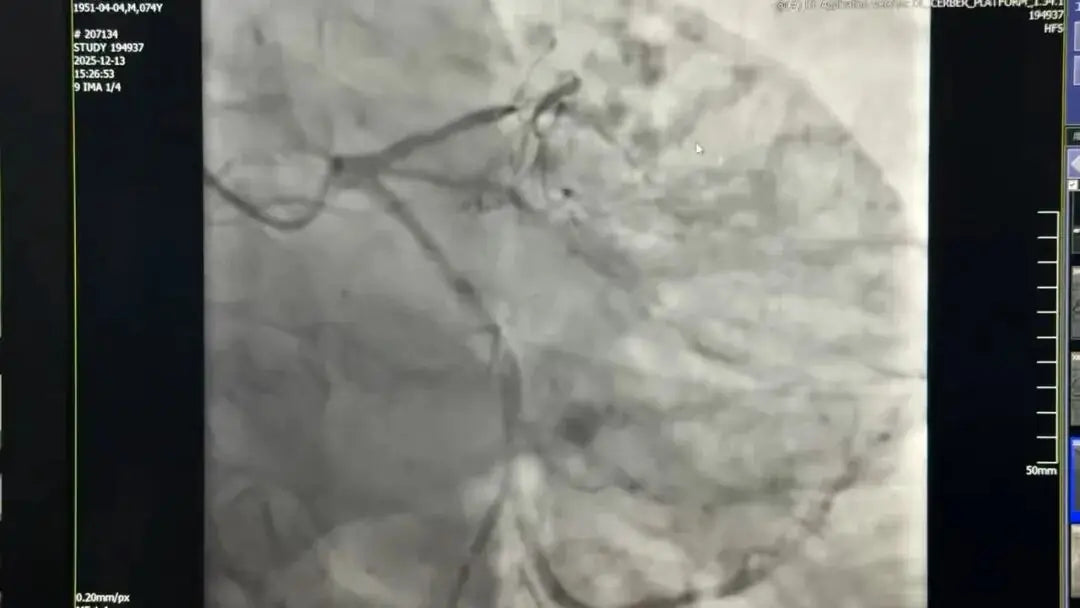

The patient, Mr. Yang (74), was referred to Fu Wai Hospital due to severe angina and dyspnea over the past year. Angiography revealed complex coronary anatomy, including a CTO, and extensive, dense diffuse calcification lining the vessel walls—a scenario local hospitals deemed too risky to manage.

Technical Breakthrough: Carving a Path of Life Through "Stone" Facing the extreme challenge—where the guidewire failed to penetrate the calcification in the antegrade approach and the retrograde path was blocked by complex anatomy—Dr. Yang Honghui’s team meticulously planned and opted for the "Atherectomy + Precise Stenting" strategy:

• Rotational Atherectomy (RA): The team deployed a high-speed rotating burr to precisely "grind" the hardened calcified plaque into fine particles. This required exceptional dexterity and control, likened to "carving a path through stone."

• Precision Recanalization and Reconstruction: Once the pathway was successfully opened via RA, the team meticulously delivered and deployed the final stent, achieving complete recanalization and reconstruction of the occluded vessel.